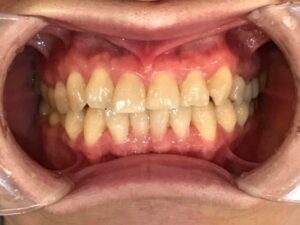

■治療前の状態

初診時、前歯を中心に歯の重なりが強く見られました。特に下顎前歯部はスペース不足によりねじれや段差が生じており、審美性だけでなく清掃性にも課題がある状態でした。

また、CT診断およびセファロ分析(ceph1.jpg)により、骨格的な大きなズレはなく、歯の移動で改善可能と判断しました。